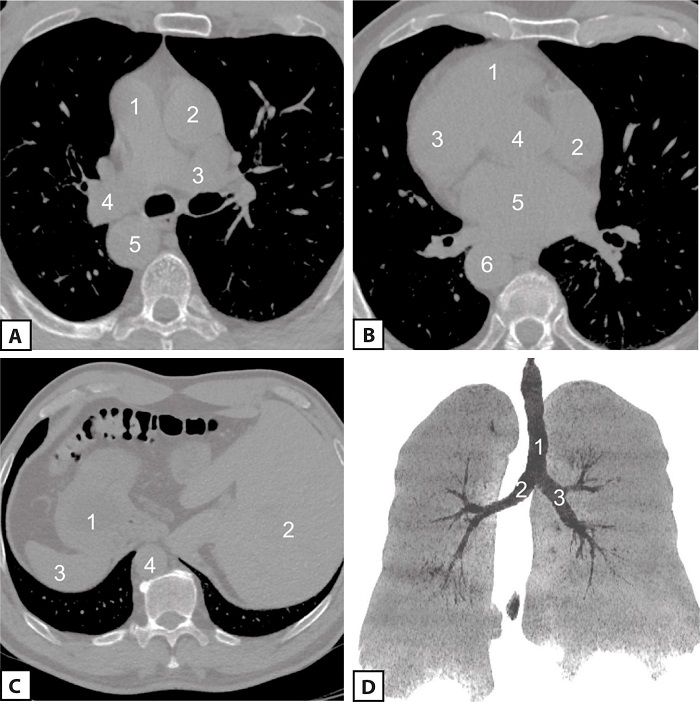

When setting out for the upcoming surgery, it was considered reasonable to perform an additional multislice computed tomography (Figures 3 A, B, C, and D).